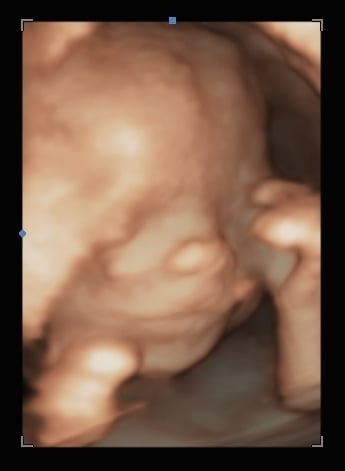

Hoping this works-ive never uploaded on here from a phone. This is sweet baby at 17+5 for our anatomy scan. We aren't finding out sex, so still using interchangeable pronouns and avoiding calling the baby "it". Babies nickname has been Batman since the beginning (cause....why not). Since we didn't get a great face shot to do measurements, I get to go back in 8 weeks for another. Which I am secretly thrilled about. This picture is SUCH a change from babies first photo shoot at 5+6!